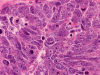

The cytologic preparation demonstrates scattered to small clusters of small blue cells with a "dirty background" (Panel A). In general, the nuclei are round to oval and with a hyperchromatic, coarse salt and pepper like nucleoplasm. Many cells with pyknotic or apoptotic appearing nuclei are noted (Arrows in Panel A and B). A large, prominent nucleoli can be seen in many tumor cells (Arrow in Panel C). There is also large variation of tumor size (Panel D). The histopathologic picture of frozen sections (Panel D and E) is consistent with a small blue cell tumor. Note that the the nuclear details is poorly preserved. In general, nuclei of small blue cell tumors are much better demonstrated on cytologic preparation than frozen section. The frozen section, however, gives the overall architecture of the tumor.

On permanent sections, there is extensive necrosis (Panel G) and there are numerous small islands of pyknotic or apototic nuclei (Panel H). In non-necrotic areas, the nuclei are large and pleomorphic. There are numerous mitotic figures (Panel I). Nuclear wrapping (Arrow in Panel J) is readily seen. The tumor is focally positive for synaptophysin, neurofilament proteins, glial fibrillary acidic protein, and diffusely positive for antibody BAF47.

Large cell (anaplastic) medulloblastoma is characterized by large, vesicular nuclei that are 5 times or more the size of a red blood cell. Marked variation in nuclear size and contour, and multinucleated, bizarre giant cells are other features. In particular, nuclear hugging or nuclear wrapping which refers one nucleus being surrounded by other nuclei as illustrated in this cases is a classic features of large cell medulloblastoma. In contrast to the classic type of medulloblastoma, the nucleoli are prominent, necrosis is prominent and extensive, extensive apoptotic or pyknotic cells are common. Large cell medulloblastomas have numerous mitotic figures that far exceed what would be expected in a classic medulloblastoma. Attempts has been made for a grading system of anaplstic changes in medulloblastoma 1 but the value of this system still has to stand the test of time 2, 3.